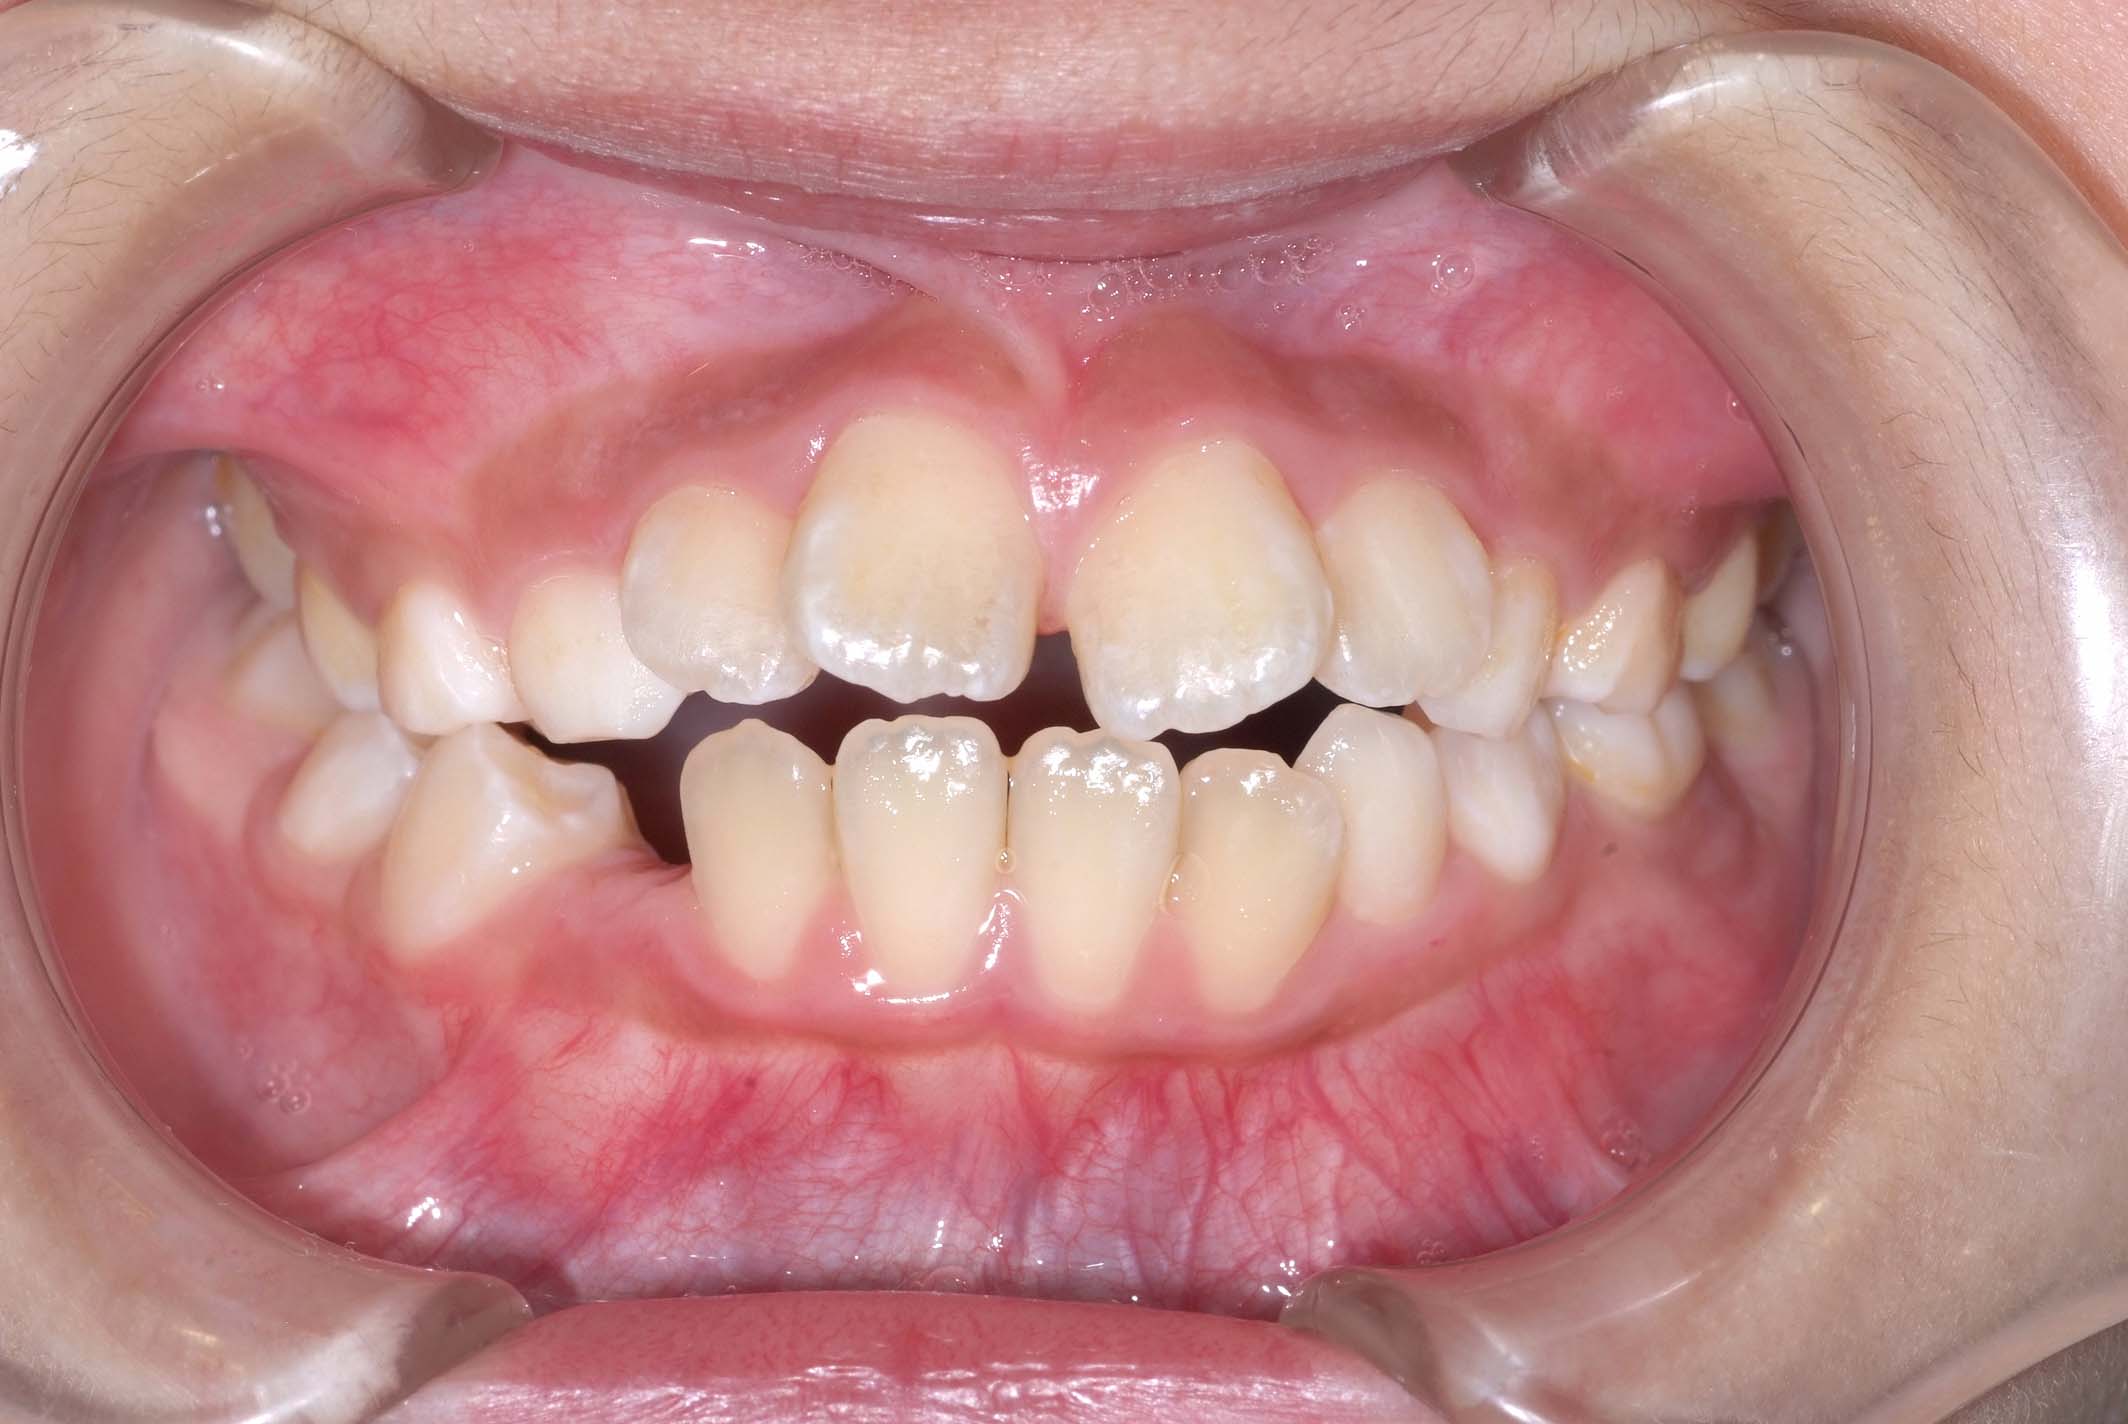

初診時年齢8才の女子で、前歯部開咬を気にして来院されました。

検査の結果、前歯部開咬と正中離開と上下顎前歯唇側傾斜を伴うアングルⅡ級1類不正咬合と診断しました。

前期治療は、リンガルアーチで正中離開を改善し、その後は歯列矯正用咬合誘導装置(マイオブレース)を使用して舌のトレーニングを行いました。後期治療は、上下左右4番を抜歯の上、セルフライゲーションブラケット装置(クリアティ・ウルトラ)で行いました。治療期間は前後期合わせて6年6ヶ月でした。通院回数:60回。